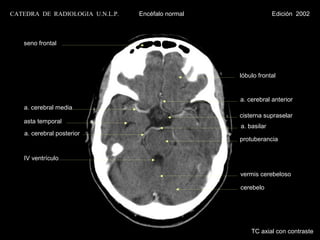

CATEDRA DE RADIOLOGIA U.N.L.P.   Encéfalo normal                Edición 2002

seno frontal

lóbulo frontal

a. cerebral anterior

a. cerebral media

cisterna supraselar

asta temporal

a. basilar

a. cerebral posterior

protuberancia

IV ventrículo

vermis cerebeloso

cerebelo

TC axial con contraste